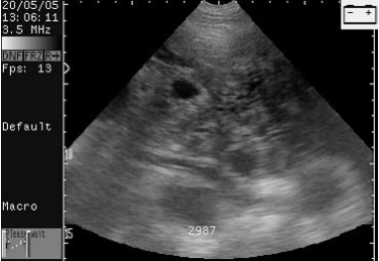

有囊肿的空怀母猪。这头母猪永远不会怀孕。

Scan of empty sow with cysts. This sow will never be pregnant.

有一个副卵巢囊肿的母猪。这头母猪能够怀孕。

Scanning of sow with one paraovarian cyst. This sow could get pregnant.

扫描配种第24天的母猪,大的胚胎囊可以很容易的看到。

Scans day 24. Large embryos bladders which are easy to see.